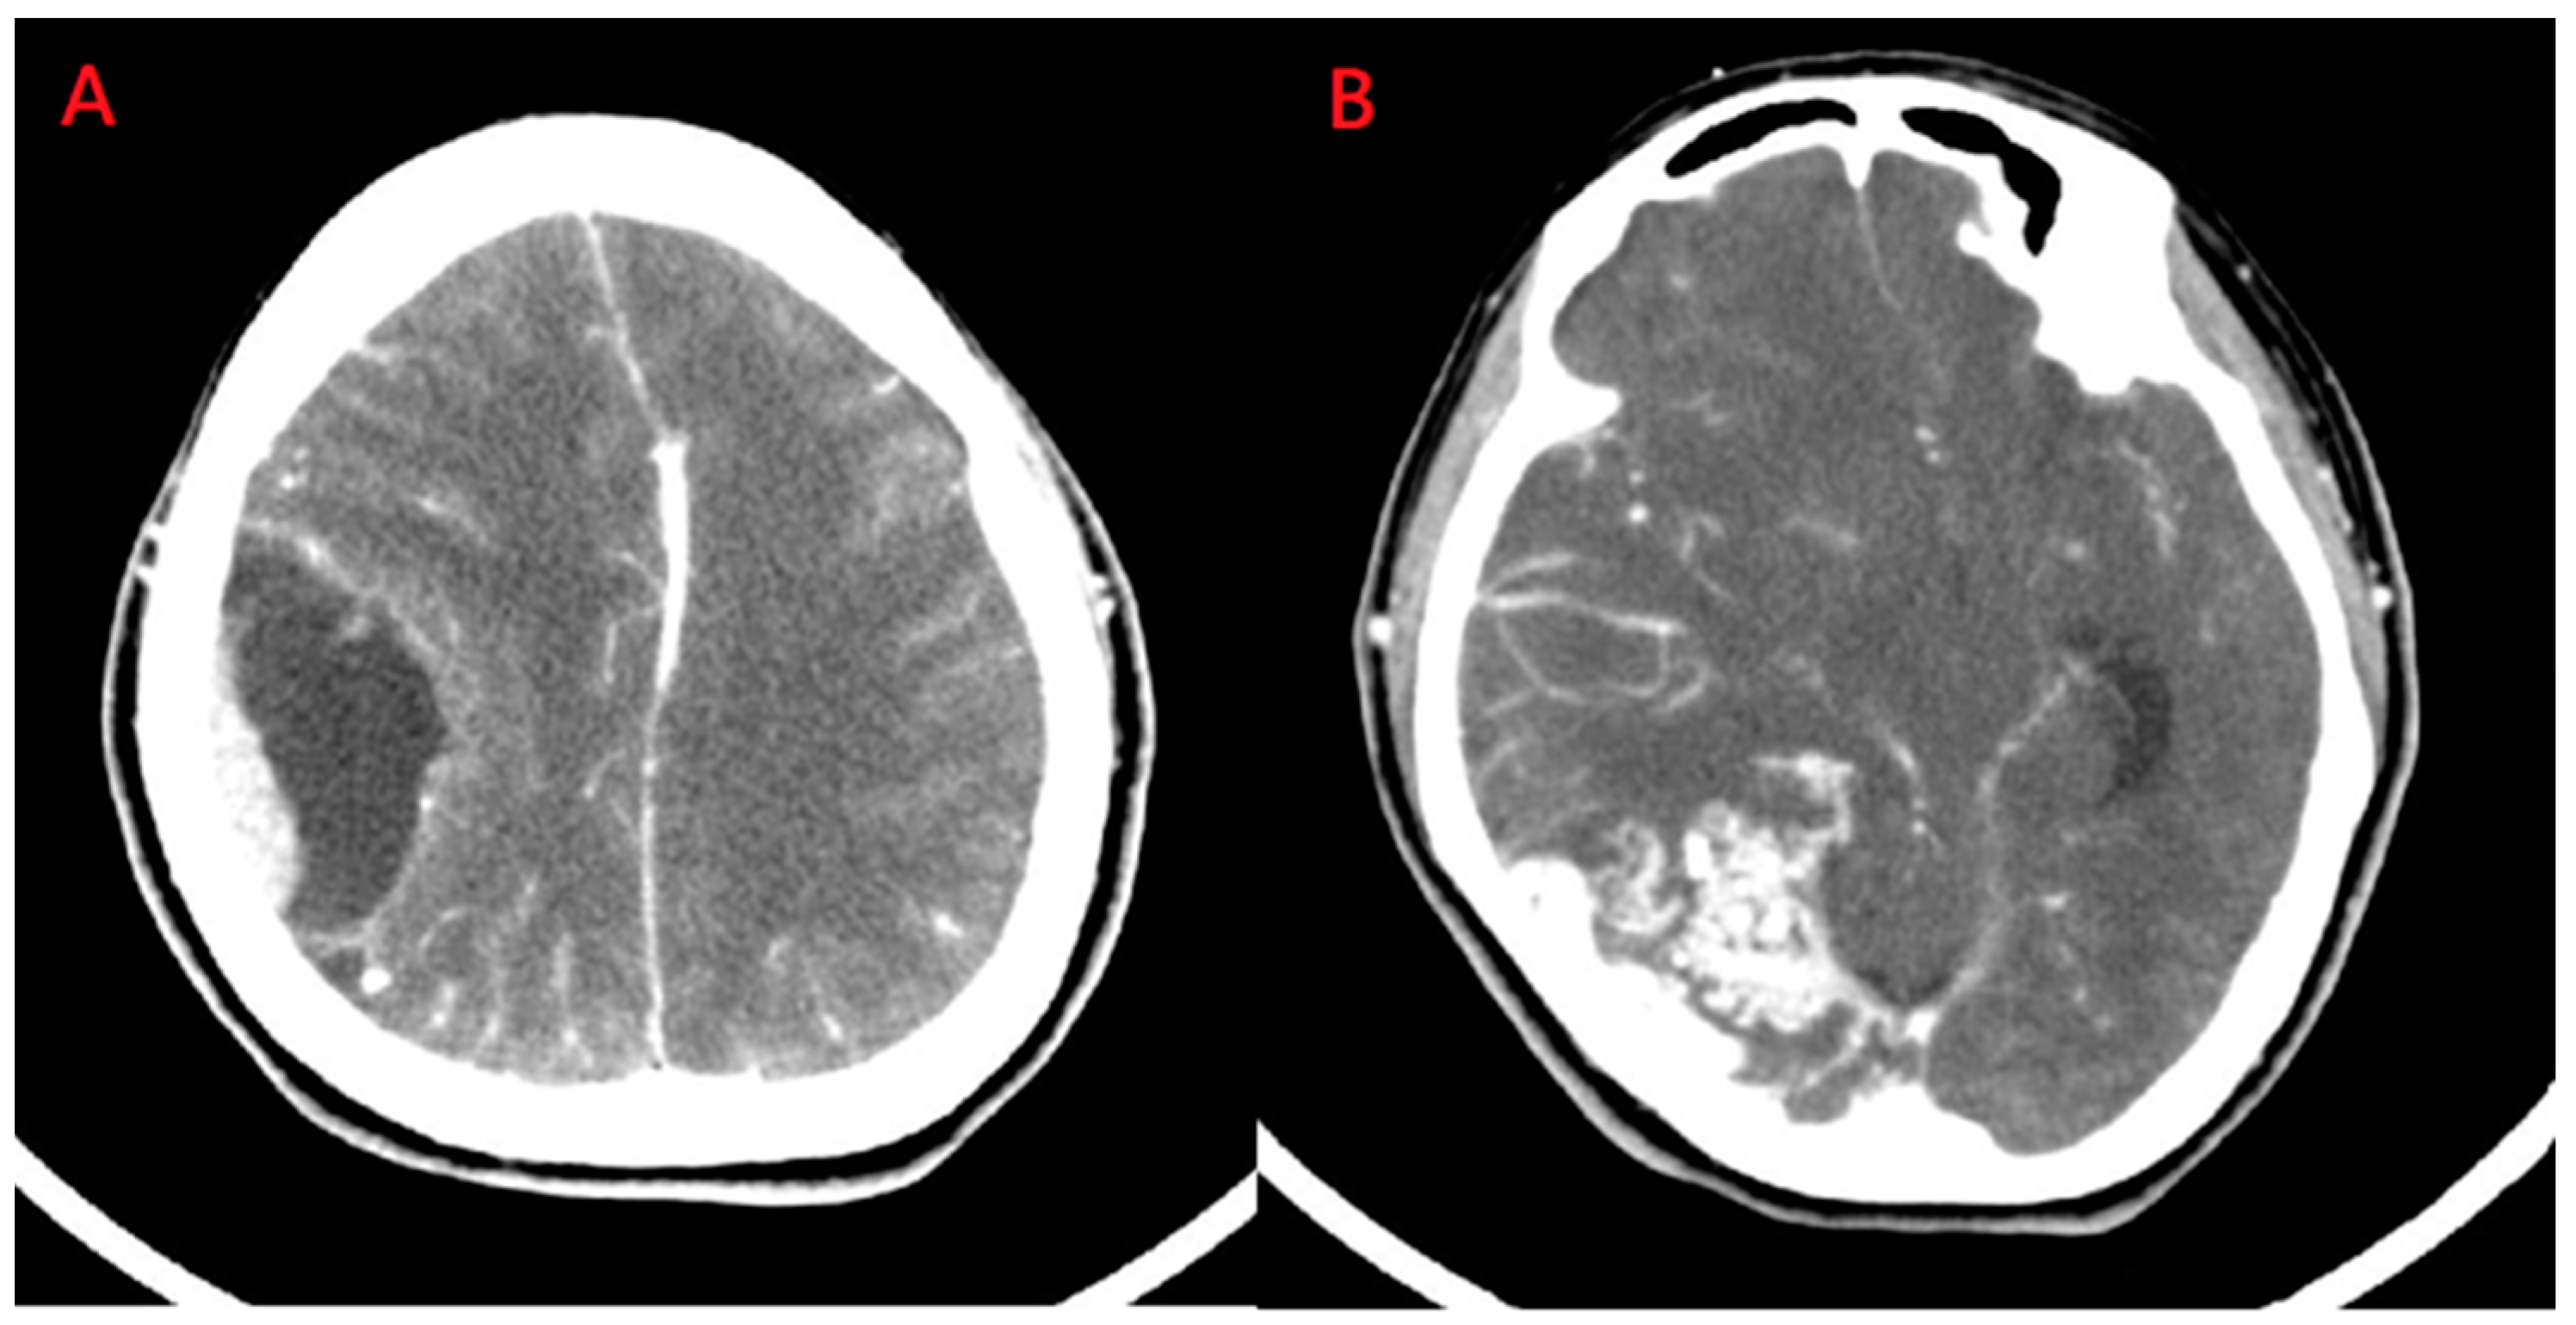

A 44-year-old female was presented to our hospital experiencing intermittent headaches and dizziness. Furthermore, she had experienced a change in consciousness three times in the previous month. Her neurological examination was normal except for slight paresthesia in her right hand. Computed tomography demonstrated enhancement with a peri-focal edema lesion over the right temporo-parietal area Figure 1A. Additionally, another lesion with focal heterogeneous enhancement was noted over the right parieto-occipital region Figure 1B.

Figure 1.

Computed tomography of brain. (A) The lesion with perifocal edema was seen in the right temporo-parietal area; (B) Another lesion with focal heterogeneous enhancement and a surrounding multilinear contrast structure with a lower density and calcified spots was noted in the right parieto-occipital region.